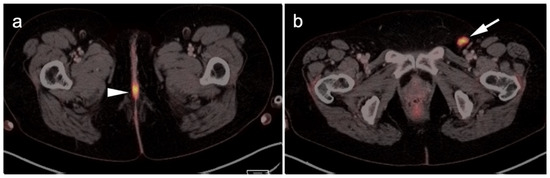

PET in Clinical Oncology | SpringerLink。Tumor Characterization by [68Ga]FAPI-46 PET/CT Can Improve。PET Molecular Imaging: A Holistic Review of Current Practice。PETによるがん診断の専門書で、詳細な技術情報を提供。PET-CT in Clinical Adult Oncology: I. Hematologic Malignancies。- タイトル: PET in Clinical Oncology- 著者: Helmut J. Wieler, R. Edward Coleman- ISBN: 978-3-7985-1219-1- 出版社: Springer- 言語: 英語- 内容: PETによるがんの診断と治療に関する詳細な情報を提供する専門書。。ご覧いただきありがとうございます。エピソード薬物動態学 薬物動態学の解明 第2版。

• PET in Clinical Oncology | SpringerLink

• Tumor Characterization by [68Ga]FAPI-46 PET/CT Can Improve

• PET Molecular Imaging: A Holistic Review of Current Practice

• PET-CT in Clinical Adult Oncology: I. Hematologic Malignancies